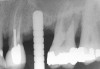

First, a periapical radiograph is taken to determine the amount of bone subantrally. It should be noted that a periapical film has an average error of 14%.23 Therefore, it is advantageous to take the radiograph in a manner that includes a marker (5-mm wide ball bearing) in order to be able to calculate the magnitude of radiographic error (Figure 1).

Figure 1  At tooth site No. 14, a periapical radiograph was taken with the long-cone paralleling technique. The radiographic ball marker measured 5.8 mm while its actual diameter is 5 mm. The enlargement is 0.8 mm, therefore the magnification error is 0.8/5 = 16%. By correcting for this error, a closer approximation of the amount of bone from the osseous crest to the sinus floor can be made.

Figure 1